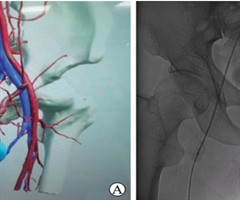

腹壁下动脉-阴茎背深静脉吻合术治疗动脉性勃起功能障碍1例报告

中图分类号:R698.2 文献标志码:B DOI:10.3969/j.issn.1009-8291.2025.06.016 在严格把握好适应证的前提下,阴茎动脉血管重建手术可能是动脉性勃起功能障碍(erectiledysfuction,ED...